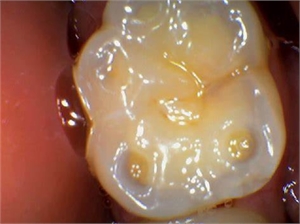

Wear facets caused by bruxing on the chewing surface of molar

Sometimes, the surface of your teeth might appear worn out. This worn out appearance resembles a plane polished tooth surface, whose edges may be sharp or rounded. The worn out surface can be any tooth surface. It might be the surface that helps in chewing, the surface that corresponds to the cheeks or the surface in proximity to the tongue.

Literally, facet refers to one side of a structure with multiple surfaces. Wear facets are caused by mechanical or chemical factors that have nothing to do with tooth decay. The occurrence of these facets can be explained through processes called attrition, erosion, abrasion and abfraction.

'Atterere' is a word in Latin which mean rubbing against something. Attrition occurs when the upper and lower teeth are grinded against each other so harshly that it goes on to wear the chewing surfaces of the teeth. It gets worse in people with deep bite as the attrition forces act on those surfaces of the teeth that correspond to the cheeks (buccal) and the tongue (lingual/palatal). In some cases a coarse diet may also lead to wear facets. The abnormal grinding of the opposing teeth is many a times seen in people with a habit of firmly clenching of their teeth (bruxism). In some other cases, a tooth may get worn out, if it is grinded against an opposing tooth bearing a porcelain crown.